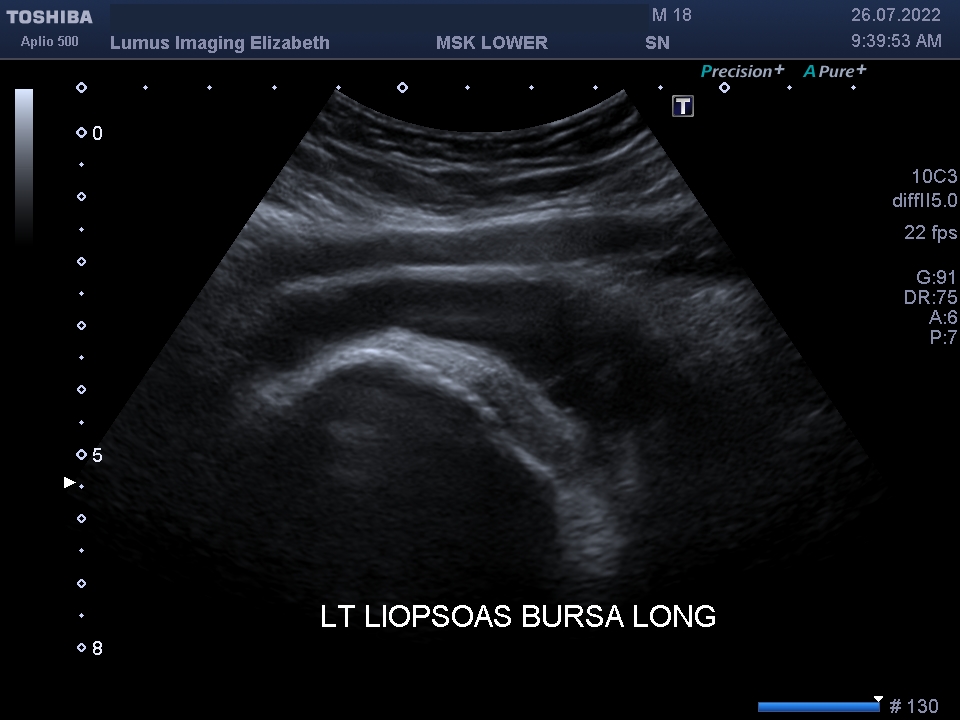

I202207261120146360024

Son Nguyen

26/07/2022